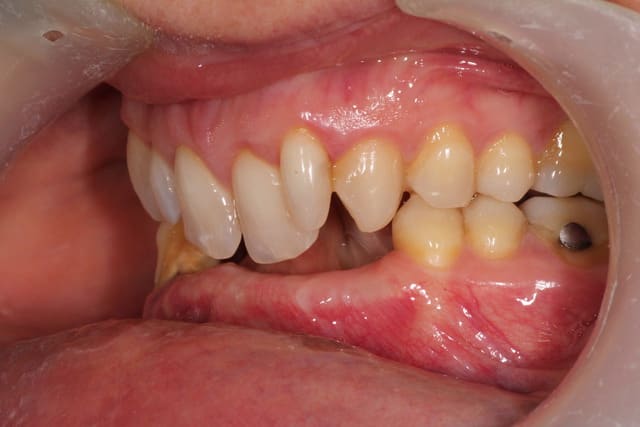

Autre cas, un peu plus ardu a mon avis.

J'ai un conseil alsacien pour un coffrage. Mais pour un premier prélèvement postérieur, c'est pas l'intervention la plus simple, compte tenue du peu de volume en rétromolaire.

le plan de traitement consiste a poser 4 implants 43 42 33 32 et un bridge de 6 éléments.

Je viens d'extraire 42 et de débuter l'ortho.